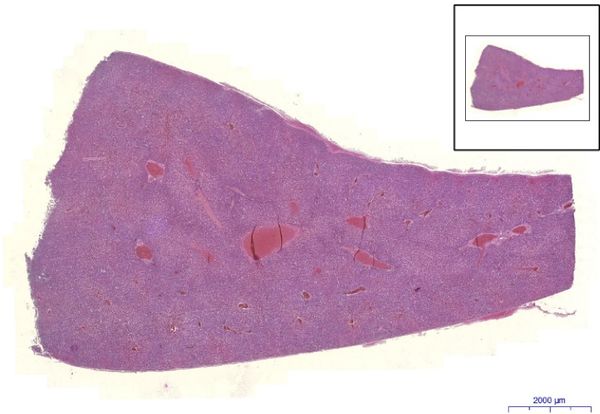

Liver - HE

Liver, HE 0,7x